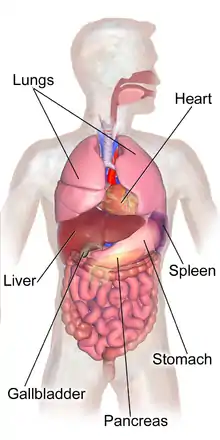

The human abdomen and organs which can be found beneath the surface | |

The abdomen (colloquially called the belly, tummy, midriff, tucky or stomach) is the part of the body between the thorax (chest) and pelvis, in humans and in other vertebrates. The abdomen is the front part of the abdominal segment of the torso. The area occupied by the abdomen is called the abdominal cavity. In arthropods, it is the posterior tagma of the body; it follows the thorax or cephalothorax.[1]

The abdominal cavity contains most organs of the digestive system, including the stomach, the small intestine, and the colon with its attached appendix. Other digestive organs are known as the accessory digestive organs and include the liver, its attached gallbladder, and the pancreas, and these communicate with the rest of the system via various ducts. The spleen, and organs of the urinary system including the kidneys, and adrenal glands also lie within the abdomen, along with many blood vessels including the aorta and inferior vena cava. The urinary bladder, uterus, fallopian tubes, and ovaries may be seen as either abdominal organs or as pelvic organs. Finally, the abdomen contains an extensive membrane called the peritoneum. A fold of peritoneum may completely cover certain organs, whereas it may cover only one side of organs that usually lie closer to the abdominal wall. This is called the retroperitoneum, and the kidneys and ureters are known as retroperitoneal organs.

Functionally, the human abdomen is where most of the digestive tract is placed and so most of the absorption and digestion of food occurs here. The alimentary tract in the abdomen consists of the lower esophagus, the stomach, the duodenum, the jejunum, ileum, the cecum and the appendix, the ascending, transverse and descending colons, the sigmoid colon and the rectum. Other vital organs inside the abdomen include the liver, the kidneys, the pancreas and the spleen.